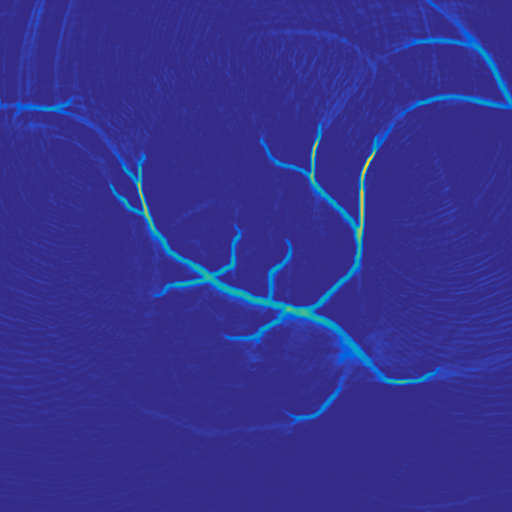

A 2D scenario: Ω=[0,1]2Ωsuperscript012\Omega=[0,1]^{2} with inhomogeneous medium properties and an irregular sensor geometry, see Figure 1. The medium properties vary in the range encountered, e.g., in the human breast [19].

Figure 1: 2D PAT scenario (II) used in the numerical studies. The spatial resolution is N=5122𝑁superscript5122N=512^{2} plus 242424 pixels of PML layer in all directions. LABEL:sub@subfig:2DScenarioA The scenario cosists of three materials: Material A (covering the top part of the domain): c=1500𝑐1500c=1500, ρ0=1000subscript𝜌01000\rho_{0}=1000, material B (parabolic-like part): c=1400𝑐1400c=1400, ρ0=1200subscript𝜌01200\rho_{0}=1200, material C (vessel-like part): c=1560𝑐1560c=1560, ρ0=800subscript𝜌0800\rho_{0}=800. LABEL:sub@subfig:2DScenarioB Ground truth p0subscript𝑝0p_{0} and sensor configuration (white pixels, 200200200 sensors at the interface between materials A and B.)